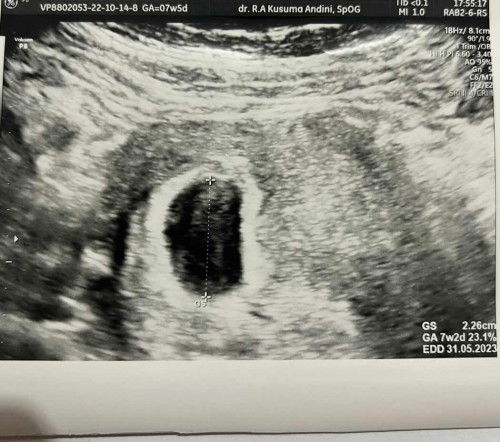

Sebenernya aku dr umur 14w udh keluar bun tp makin kesini umur 17w baju sering basah dan jd kerak. Padahal tidak pernah dipancing atau dipencet. Bagaimana ya bun solusinya? Dokter kandungan menyarankan di pumping. Tp bukannya pumping diusia segini bisa menyebabkan kontraksi dini ya? Apakah ada yg sama? Boleh share yaa#firstmom #ingintahu